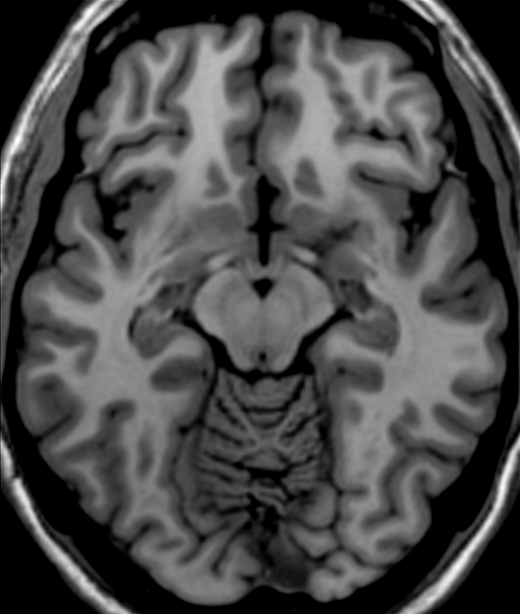

Name and point at the specific location of the cells bodies that are involved in the pathology of Parkinson's Disease